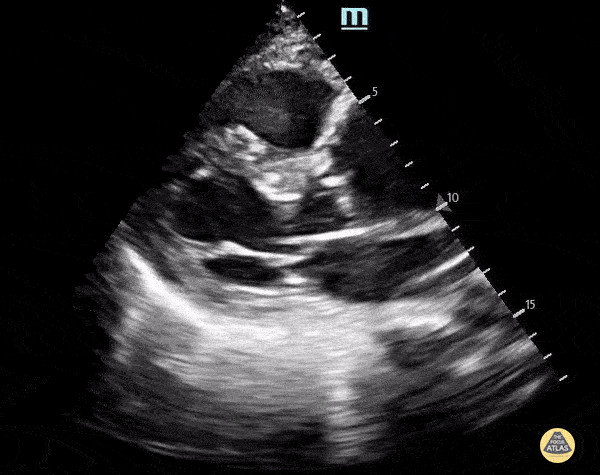

A 70 y.o. male presented with altered mental status. POCUS echocardiogram performed in the ED revealed an ascending thoracic aortic aneurysm measuring approximately 5 cm in diameter (parasternal long-axis view shown here). A chart review revealed that the patient does indeed have a history of TAA, and a comparison of our findings to a prior CTA demonstrates no significant increase in diameter. Nevertheless, this study demonstrates the utility of POCUS in the rapid and early detection of ascending aortic abnormalities. Alex Schlangen, D.O. PGY-1 EM Resident at Central Michigan University; Andrew Namespetra, MB BCh BAO. @AndrewNamespet1 PGY-3 EM Resident at Central Michigan University